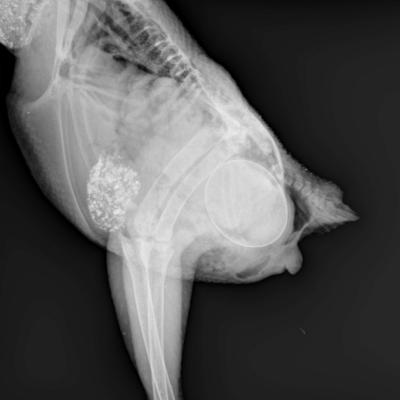

Retention d'un oeuf sur un oiseau